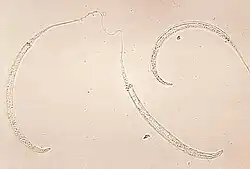

Гельминтоз, передающийся через почву, является наиболее распространенным забытым тропическим заболеванием[67].Три основных вида червей, ответственных за гельминтозы, передаваемые через почву, — это Ascaris (круглые черви), Trichuris (власоглав), анкилостомы Necator americanus и Ancylostoma duodenale, а также Strongyloides stercoralis[68]. В настоящее время инфицировано 1,5 миллиарда человек[68]. Геминтоз, передаваемый через почву, встречается в странах Африки к югу от Сахары, Северной и Южной Америке, Китае и Восточной Азии[68]. Риск смертности очень низок[16] .Наиболее распространенными симптомами являются анемия, задержка роста, проблемы с кишечником, недостаток энергии и нарушение физического и когнитивного развития[16][68]. Инфицированные дети часто отстают в учёбе[16]. Тяжесть симптомов зависит от количества червей в организме[68].

Паразитические черви обычно передаются через зараженные человеческие фекалии и почву, которые распространяются в окружающей среде, например, из-за открытой дефекации[68]. Наиболее распространенным методом лечения является медикаментозное лечение[68]. Его можно предотвратить с помощью гигиенически приготовленной пищи и чистой воды, улучшенных санитарных условий, периодической дегельминтизации и санитарного просвещения[68]. Всемирная организация здравоохранения рекомендует массовую дегельминтизацию без предварительной диагностики[68].